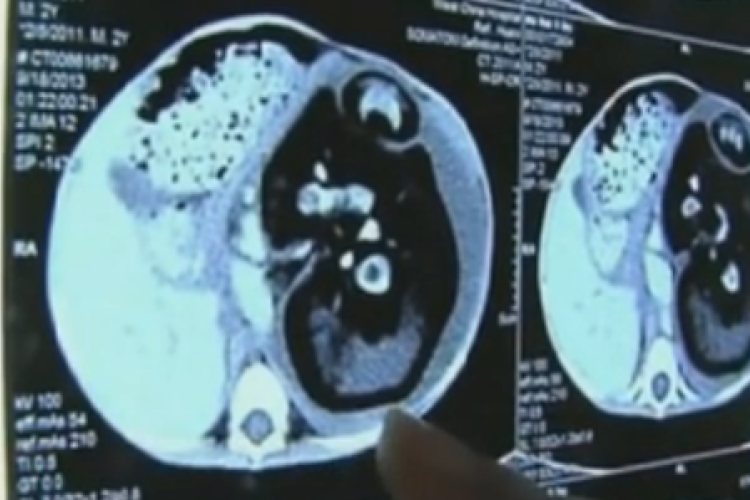

Saját testvérét szülte meg egy kétéves kisfiú (videó)

Rendkívül bizarr dolgot állapítottak meg az orvosok egy kínai kisfiúnál: a gyerek terhes, saját testvérével.